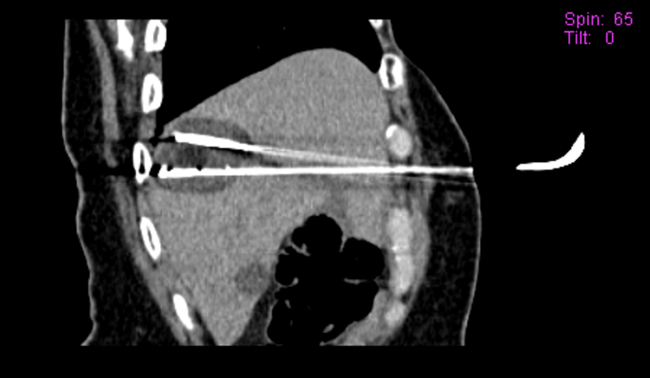

With the patient supine, 2 cryoprobes were inserted by anterior approach, and placed almost parallel in a chopsticks formation immediately above and below the lesion, in order to encase the metastasis and create a safety margin around the lesion.1

Of note, the lateral and posterior approach was not chosen to reduce the risk of unwanted puncture of the pleura and subsequent potential pneumothorax. In addition, the distance between the 2 probes was about 15 mm to optimize the synergy of action of the 2 ice balls.

At the conclusion of the freezing phase, axial, coronal, and sagittal computed tomography reconstruction (Figures 1C, 1D, 1E) showed the tumor (central hypodensity) and the ice ball as hypodensity around the tumor, enlarging the ablation area by 5/10 mm, corresponding to the safety zone.